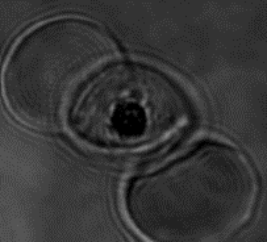

Dividing malaria parasite stained with trypan blue